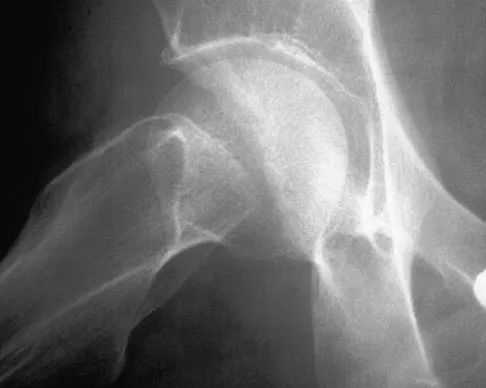

Figures 22a and 22b show the radiographs of a patient who reports stiffness of the hip and associated pain. Management should consist of

The patient has grade IV heterotopic ossification with the limb in an abnormal nonfunctional position. Treatment should consist of excision of the bone to restore hip motion and prophylaxis to prevent recurrent formation. The best time to excise the bone is controversial, with no conclusive evidence supporting early or late excision. Pellegrini VD Jr, Koniski AA, Gastel JA, Rubin P, Evarts CM: Prevention of heterotopic ossification with irradiation after total hip arthroplasty: Radiation therapy with a single dose of eight hundred centigray administered to a limited field. J Bone Joint Surg Am 1992;74:186-200.

- Warren SB, Brooker AF Jr: Excision of heterotopic bone followed by irradiation after total hip arthroplasty. J Bone Joint Surg Am 1992;74:201-210.